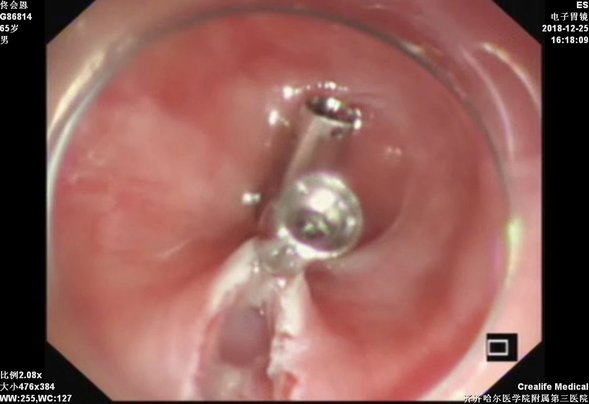

钛夹封闭隧道口